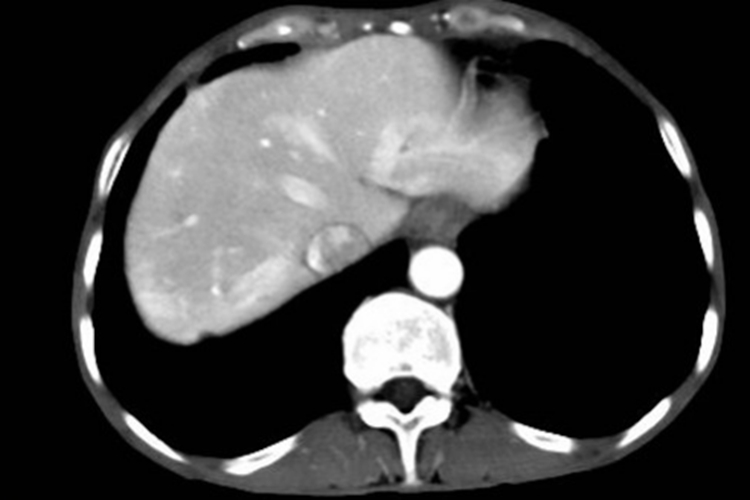

肝转移:肝是胰腺癌远处转移的最常发生部位。肝转移可以发生在胰腺癌最初诊断的时候,也可以发生在切除治疗后的随访期,可引起肝功能受损、黄疸等症状。